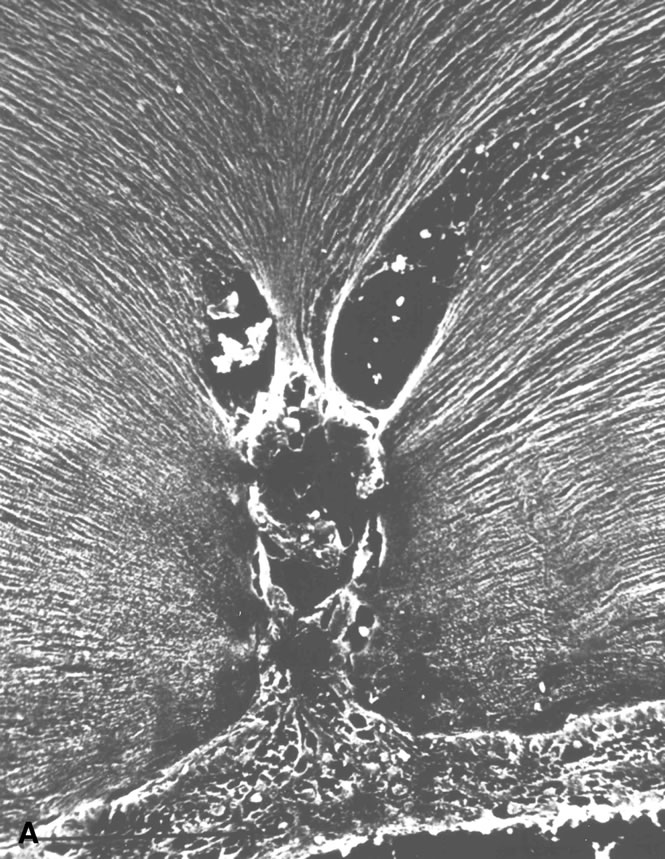

Fig. 10. A. Cystic retinal tuft. The tuft is a cystoid formation of fibers, similar to those of the nerve fiber layer, and cells similar to those found in the inner plexiform layer of the retina. The tuft is connected to the internal limiting lamina of the retina. This scanning electron micrograph shows the insertion of the vitreous collagen fibers on the tuft's apical surface. Their orientation changes toward the tuft's surface. B. Verruca. The verruca has a structure similar to that of a tree. Its “roots” are embedded in the inner layers of the retina. Cellular elements resembling cells of the inner plexiform layer can be seen near the retinal surface. The “trunk” of this structure extends from the retina to the middle parts of the vitreous cortex. The “branches” of the verruca are intertwined with interrupted vitreous collagen fibers. Local condensation of collagen fibers exists as well as local collagen destruction (arrows) and interruption of the internal limiting lamina of the retina. (Photographs courtesy of Dr. Stephan Dunker.153)